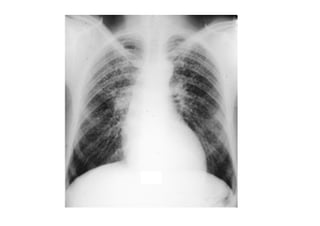

EAA: HRCT, chronic disease

Chronic Hypersensitivity Pneumonitis

• Can consist of constitutional symptoms such as wt

loss, fever and fatigue.

• Radiographic findings more c/w with typical

interstitial fibrosis – dyspnea, bilateral crackles, cxr

with reticulonodular opacities and honeycombing,

poor response to steroids.